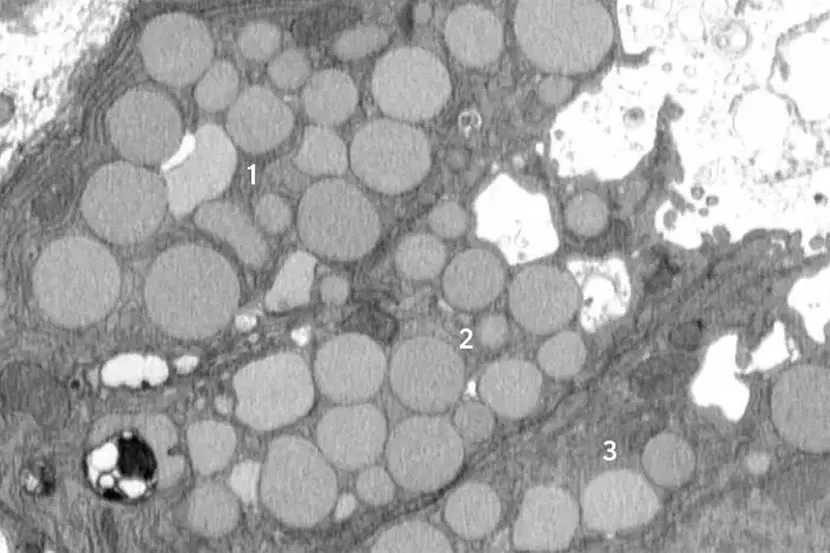

Prvobitno su istraživači pretpostavljali da se uklanjanje ćelijske mašinerije u cilju pripreme za reprogramiranje dešava potpuno unutar ćelijskih odeljaka zvanih lizozomi, gde se otpad razgrađuje u sporom i izdvojenom procesu.

Međutim, od početka su primetili otpatke izvan ćelija. Inicijalno su to zanemarili kao nevažno, ali su videli sve više eksternog otpada. Model želudačne povrede kod miševa koja je izazvala reprogramiranje zrelih ćelija u stanje matičnih ćelija, svih odjednom, pokazao je da je reakcija „povraćanja“ odlika paligenoze. Drugačije rečeno, proces povraćanja nije sporadičan, već novoidentifikovan, standardan način reagovanja ćelija na povredu.